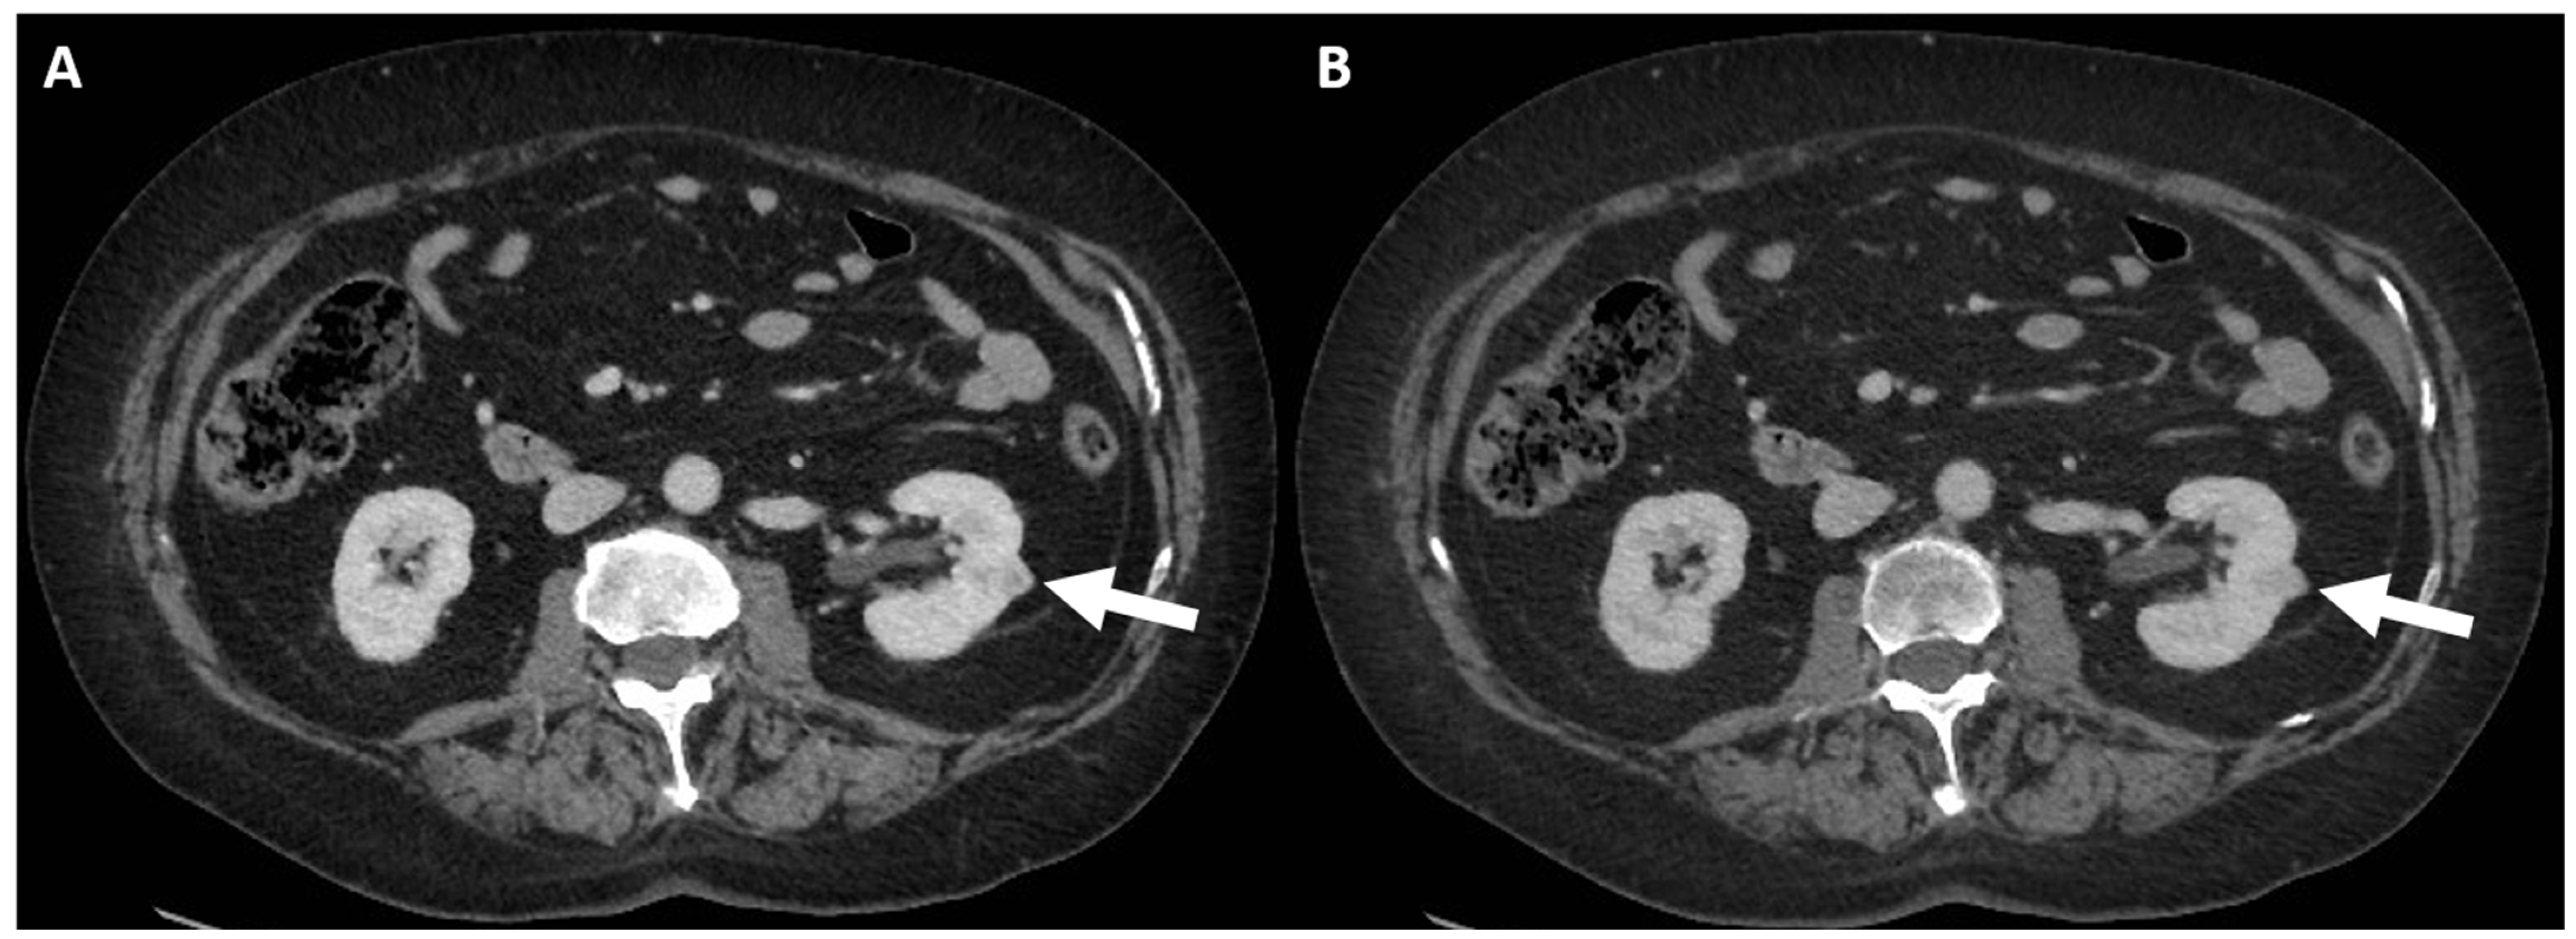

- (e) Class IV: clearly malignant cystic mass, which includes masses characterized by the presence of one or more enhancing nodules (≥4 mm convex protrusion with obtuse margins, or a convex protrusion of any size that has acute margins). A Bosniak IV mass (Figure 5) has a malignancy rate of about 90% and therefore requires urologic consultation to perform partial or total nephrectomy [100].